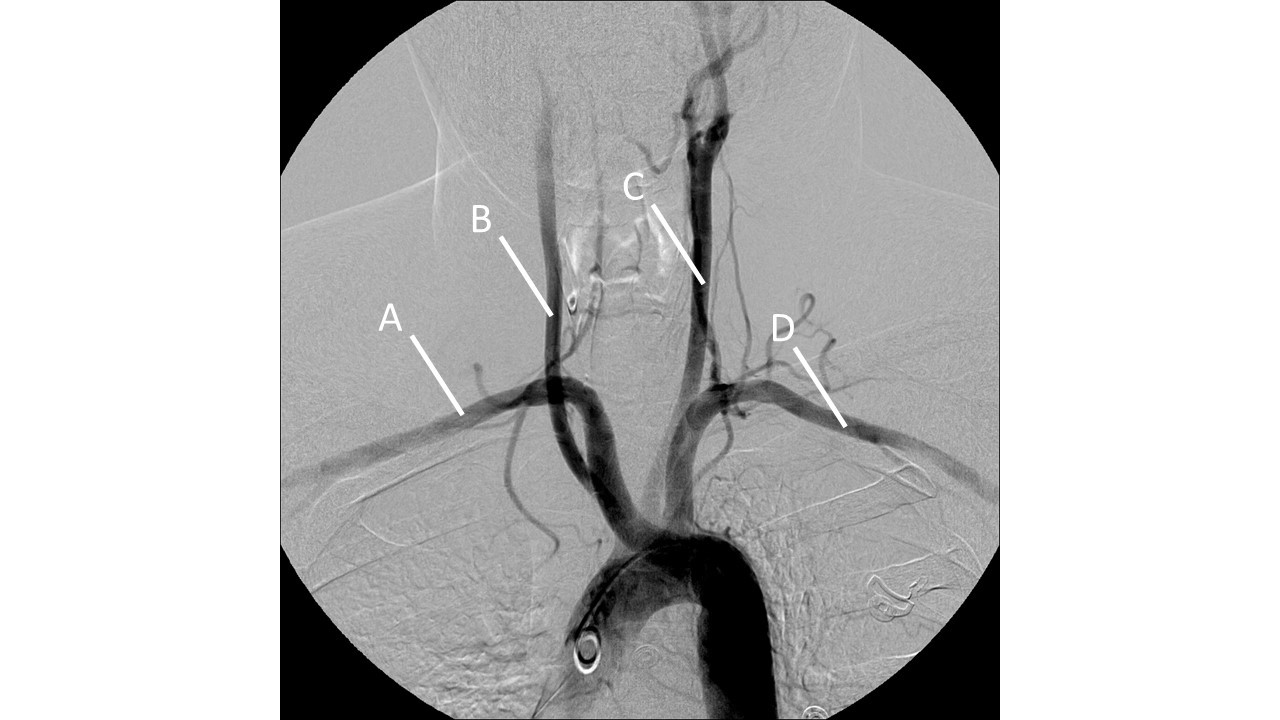

leriche syndrome (aorto-occlusive disease)

leriche syndrome

ideal femoral access location

enter skin inferomedial to the femoral head

femoral head provides a hard surface for hemostasis

at the level of the femoral head, the femoral artery and nerve are side by side